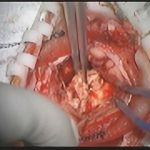

術中写真

摘出 前